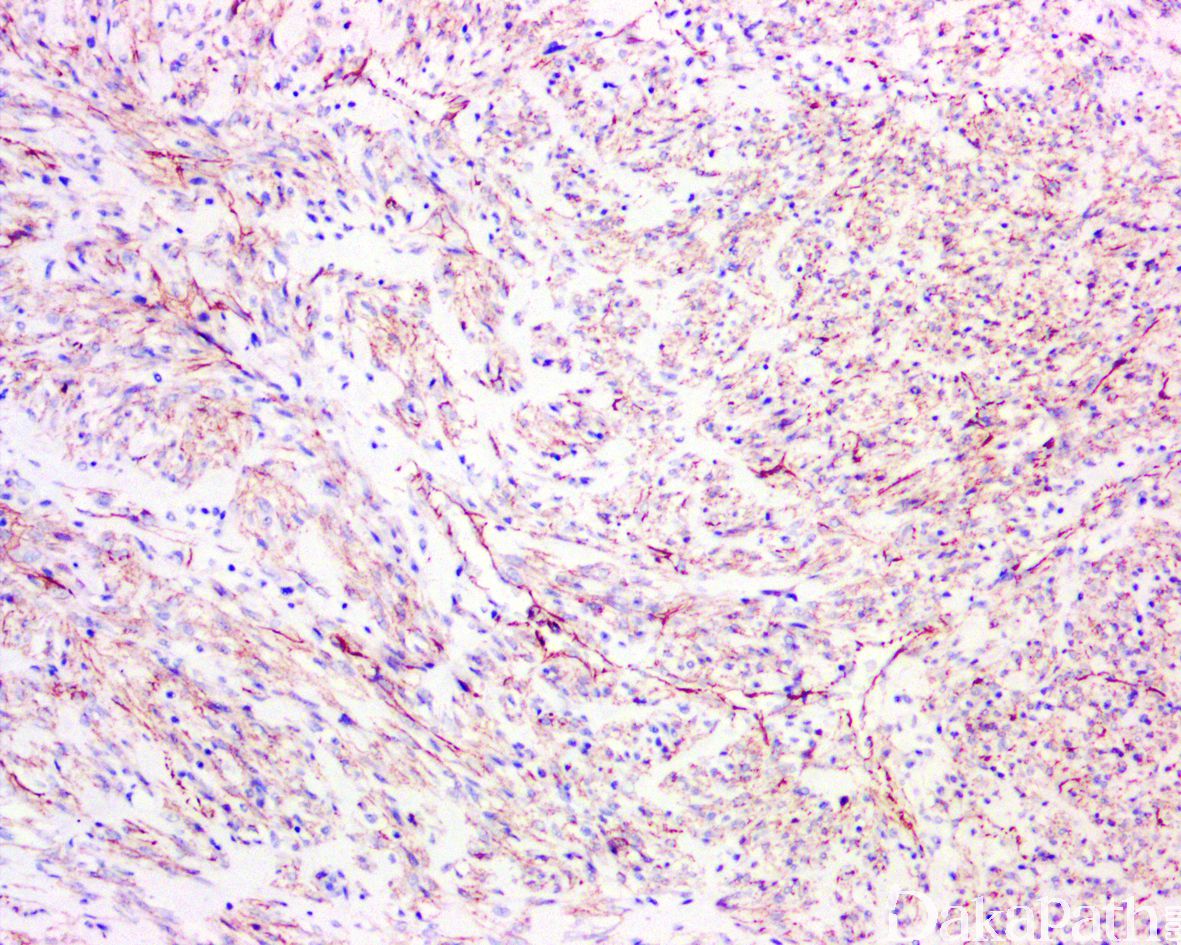

免疫组织化学染色:

SMA 常弥漫阳性,少数 desmin 局灶阳性,角蛋白、S100. CD34 及 β-catenin(核)阴性,病变内组织细胞 CD68 阳性。